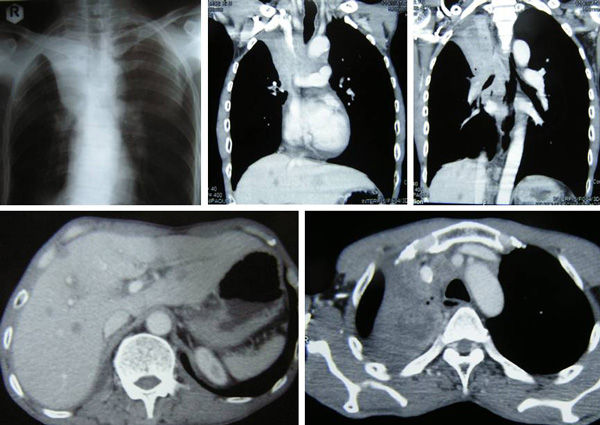

Jasmine and her family came to Penang for further consultation. Her blood test results showed CEA = 247.03 and CA 19.9 = 72.2. Jasmine was also told that her cancer had already spread to her liver. She immediately underwent an operation in Hospital A. The procedure cost her RM 60,000 plus.

The pathology report indicated:

- A moderately differentiated adeocarcinoma with metastases in pericolic lymph nodes (11/11) and segment 4a of liver. This was a T3N2Mx, Stage 4 cancer.

- The non-neoplastic liver shows features of chronic hepatitis with grade 2 activity, Stage 3.